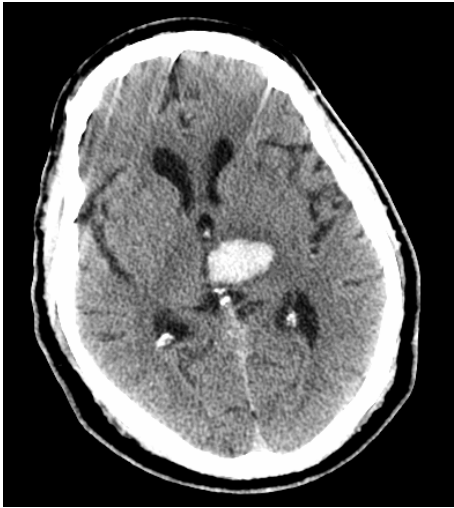

A 45 y/o woman with hypertension is resuscitated after a cardiac arrest. On day three she is able to move her face, hands, and feet, but is unable to move her limbs. A T2W1 MRI is taken at this time and is attached.

What is the general pathogenesis behind her symptoms and the MRI findings?

Hypotension secondary to cardiac arrest caused ischemia within the cerebrum, which has damaged her primary motor cortex bilaterally.

What cellular change is causing the bright vertical bands in each hemisphere?

Cytotoxic edema secondary to ischemia. The ischemia disrupts metabolism, which shuts down the Na+/K+/ATPase and causes cellular retention of Na+ and water.

Recall that on a T2W1 MRI, fluid (including water and CSF) is bright (as well as fat).

Why is the cellular change visaulized by the MRI localized to vertical bands?

This injury is a watershed infarction between the areas perfused by the ACA and MCA. The MCA area of the brain is especially susceptible to ischemia, and so its watershed area with the ACA will be the first to suffer. The bright vertical bands show cellular injury in the watershed zones across the entire cerebrum.

Why is the woman able to move her face, hands, and feet, but not her limbs?

“Man in a Barrell” pathology

Watershed injury across the the primary motor cortex tends to affect the proximal limbs and trunk much more severely than the hands, feet, and face.

• This is partially due to the watershed area’s location being centered over the motor homonculus’ area for the limbs and trunk,

• And partially due to the trunk and limbs being relatively small areas of the homonculus while the hands, feet, and face take up a large area of it (more sensitive/precise moving structures)

• Thus, even a small ischemic area can cause relatively severe truncal or limb weakness, whereas the majority of the larger face, hand, and foot regions tend to be spared.